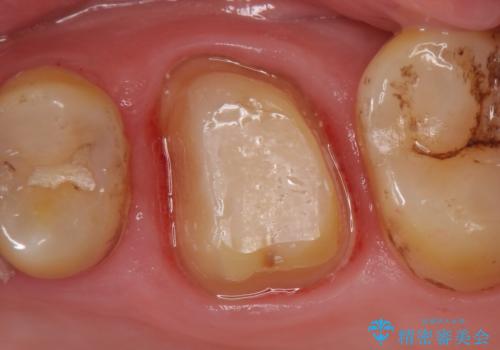

- 他院にて左上6番目の歯の神経が死んでいるといわれたので診て欲しいといらっしゃった方の症例です。

診査の結果左上6は失活していたため、根管治療を行った後にオールセラミッククラウンによる補綴を行いました。